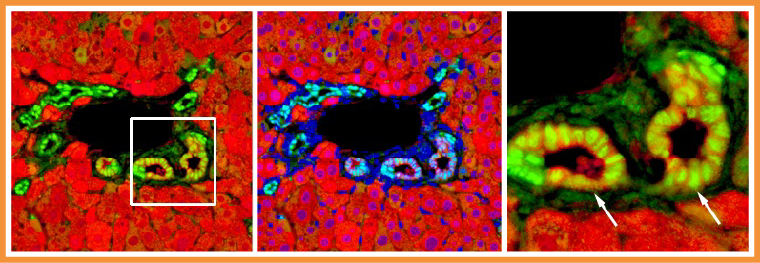

▲由肝細胞轉變而來的膽管上皮細胞。(圖/陽明交大生命科學系暨基因體科學研究所提供)

膽管的修復是肝臟多種自癒力表現之一。當膽管受損時,原本負責代謝功能的肝細胞竟能搖身一變為膽道上皮細胞,並且衝向前線修補受損的膽管。然而,這項轉變背後的分子機制長期未明。

參與研究的陽明交大生命科學系暨基因體科學研究所助理教授袁維謙表示,HBO1會被轉錄輔助因子YAP引導到特定的基因組DNA位置,就像是被派去「踩煞車」一樣,藉著表觀遺傳機制,讓原本想啟動的基因無法順利開啟,從而抑制肝細胞的轉變。如能抑制HBO1採煞車的角色,就能讓肝細胞的染色質結構加快重塑,進而促進肝細胞轉分化為功能性膽道上皮細胞,加速膽管修復。